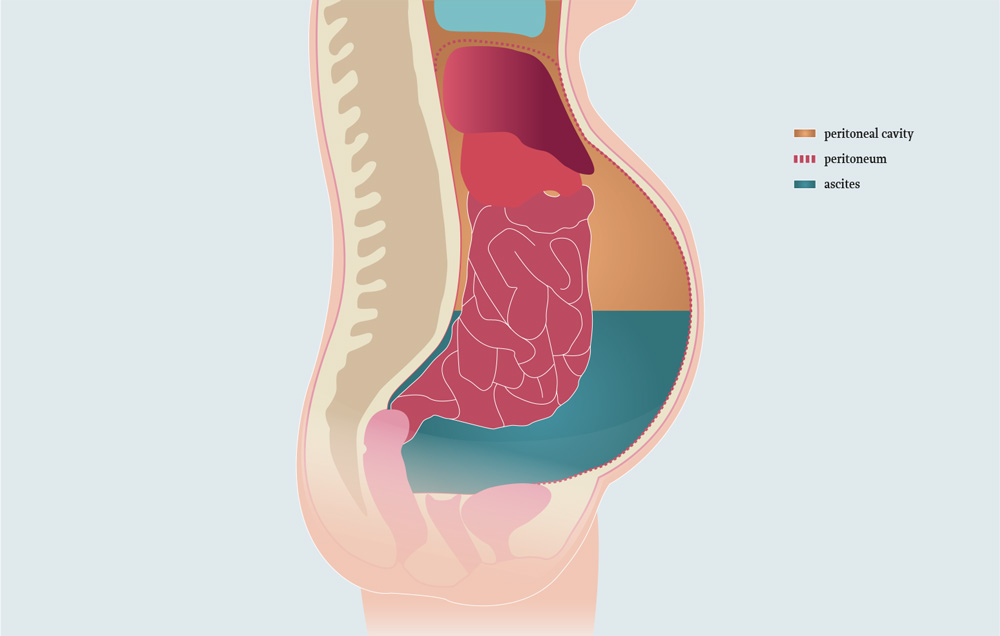

OVERVIEW

This page is dedicated to covering how the condition ascites will appear on different types of radiological imaging studies.

BASIC CHARACTERISTICS

The following are characteristic of ascites that inform its interpretation across imagine modalities:

- Density/properties similar to water: the appearance of ascites on imaging modalities is reflected by its density/properties that are similar to water.

- Exudative ascites may in some cases be more dense then water !

- Gravity dependent: given that ascites is free fluid in the peritoneal space, its location is gravity dependent.